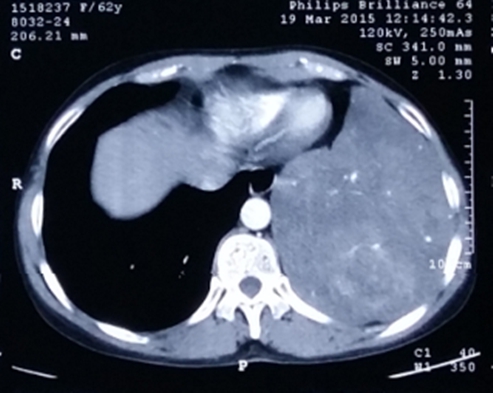

近日,我院胸外科为一位62岁女性患者成功切除胸腔内巨大罕见肿瘤。该手术的成功,标志着胸外科在肿瘤治疗领域取得新的突破。

术前检查显示,该患者胸腔内肿瘤巨大21*18*13cm,手术风险高,肿瘤切除过程中若出现大出血,止血非常困难,随时可能发生失血性休克,甚至导致死亡。另外,巨大的瘤体导致胸腔内手术操作空间局限,暴露艰难,加大了手术难度。而且该肿瘤为比较罕见的恶性孤立性纤维性肿瘤。手术风险很高,要求术中操作十分精准。

胸外科以金龙玉主任医师、曾磊主治医师为主的手术小组与手术、麻醉、输血科等相关部门对患者病情进行了认真仔细地评估,尽可能制定了一个周密的手术方案,经过精心术前准备后,历经2小时紧张而细致的“战斗”,1.65公斤重的巨大肿瘤被完整切除。在全科医护人员的共同努力下,患者顺利度过了呼吸、循环、感染“三大难关”,术后未发生任何术后并发症,恢复良好。

金龙玉主任医师手术小组今年已经连续成功切除此类病例两例。另一例为12岁少年患者,肿瘤大小为30*18*7.5cm(右侧胸腔),肿瘤重量2.25千克。